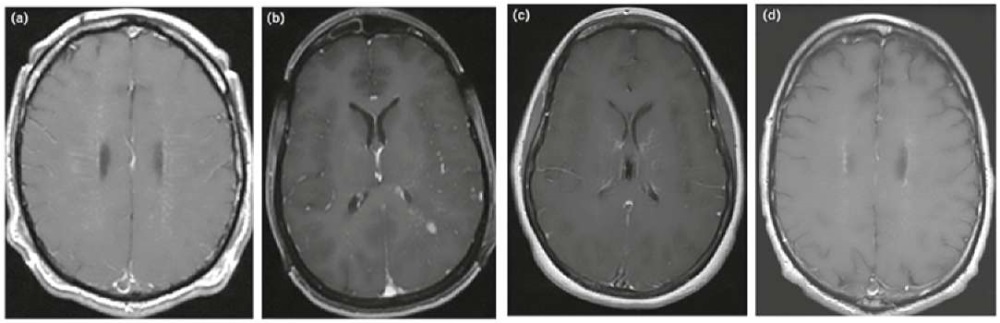

Особо специфичный МРТ-паттерн периваскулярного поражения выявляется при аутоиммунной астроцитопатии с GFAP-антителами в виде характерных радиальных и ламинарных T2/FLAIR-гиперинтенсивных очагов поражения с лептоменингеальным и линейным периваскулярным контрастным усилением в белом веществе перпендикулярно желудочкам мозга (рис. 2) [5][15].

Рисунок 2. Паттерны контрастного усиления сигнала при аутоиммунной GFAP-астроцитопатии: (a) радиальный перивентрикулярный, (b) лептоменингеальный и точечный, (c) извилистый/змеевидный, (d) периэпендимальный [15].

Figure 2. Patterns of contrast enhancement in autoimmune GFAP-astrocytopathy: (a) radial periventricular, (b) leptomeningeal and punctate, (c) serpiginous, (d) periependymal [15].